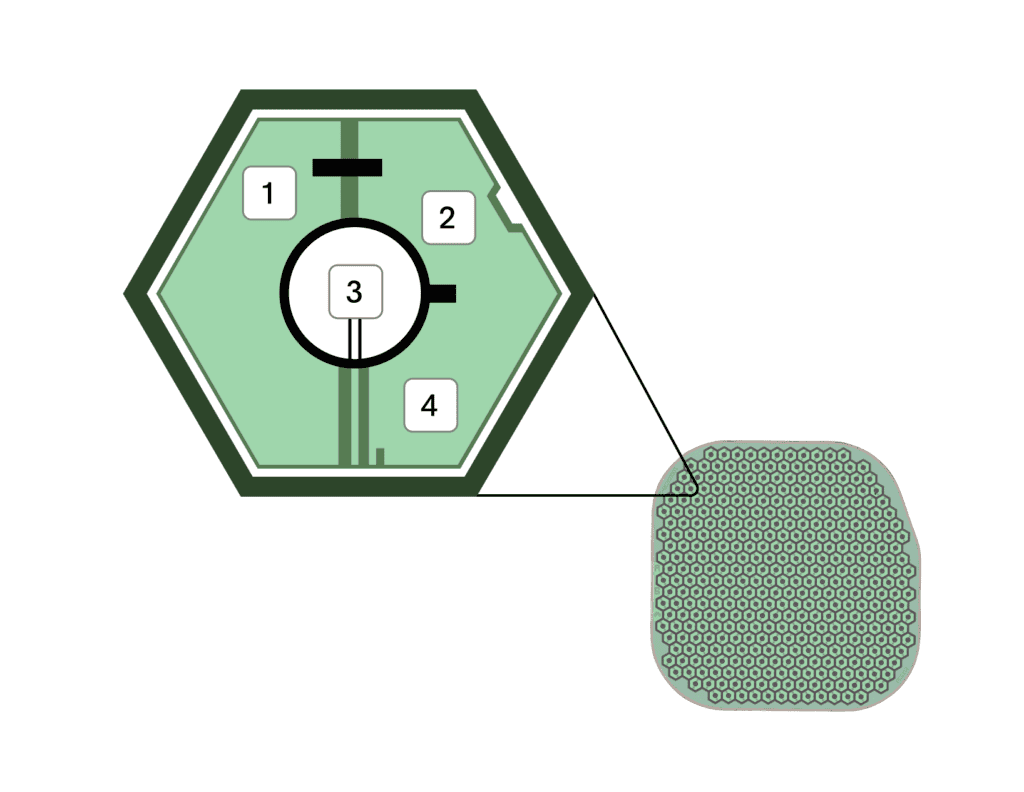

ชิป Prima ประกอบด้วยชิปสี่เหลี่ยมจัตุรัสขนาด 2 มม. ที่ถูกผ่าตัดวางไว้ใต้จอประสาทตา ตรงส่วนหลังสุดของลูกตา โดยใช้เวลาผ่าตัดนานถึง 80 นาที โดยจะใช้งานร่วมกับแว่นตาพร้อมกับกล้องที่จะบันทึกภาพ และส่งแสงอินฟราเรดไปยังชิป แล้วชิปดังกล่าวจะทำหน้าที่เสมือนแผงโซลาร์เซลล์ขนาดเล็ก ที่จะแปลงแสงเป็นการกระตุ้นไฟฟ้า และส่งไปยังสมอง จากนั้นสมองจะตีความสัญญาณดังกล่าวเป็นภาพ ซึ่งเป็นการเลียนแบบกระบวนการการมองเห็นตามธรรมชาติ